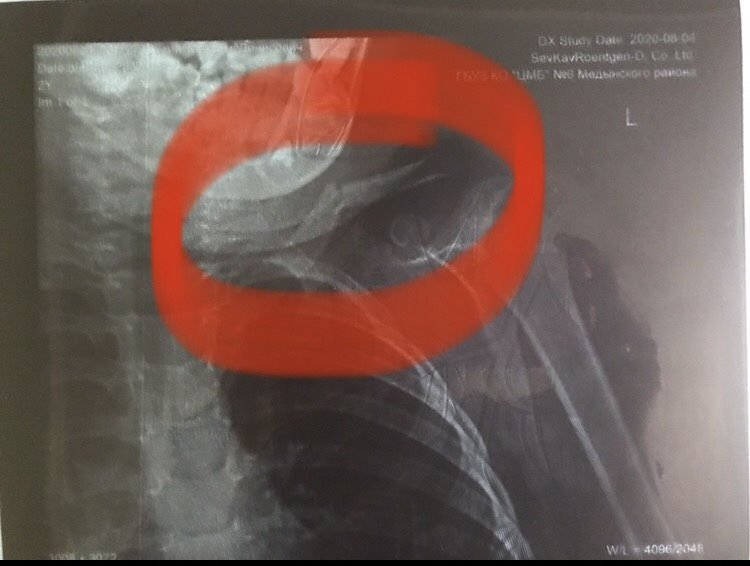

Упал с лестницы - перелом ключицы .....🤦🏽♀️ едем 🚘 в Калугу по направлению из ПК за консультацией ... Днюха в гипсе😥 хочу стереть 2020-й со всем что с нами произошло в этот год....😖

#переломключицы